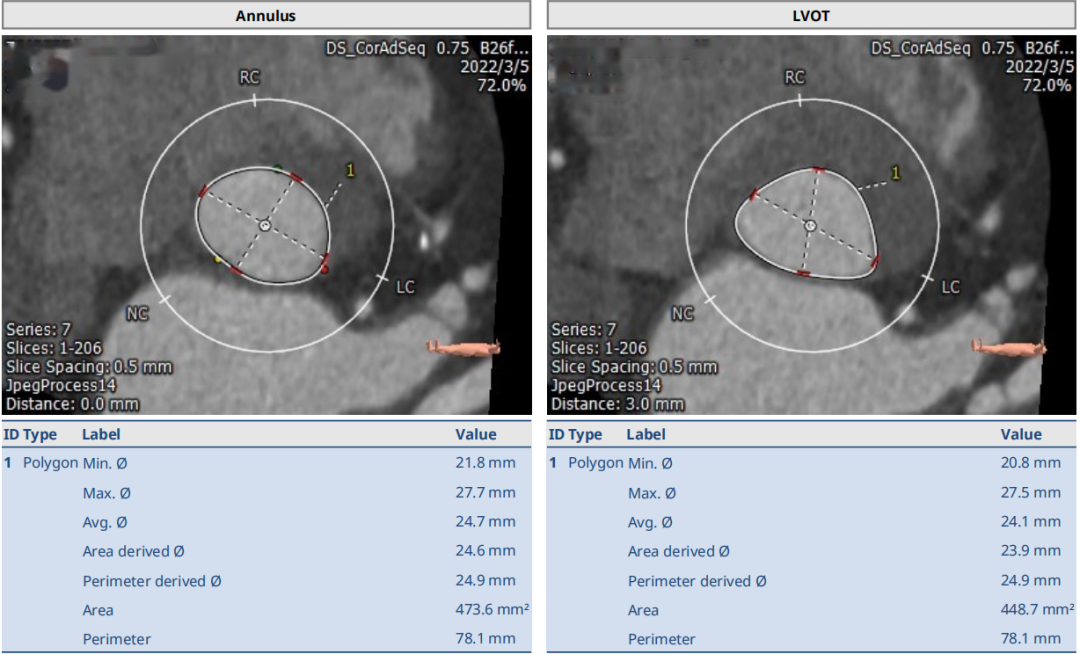

术前CT结果显示:主动脉瓣口面积473.6mm²,瓣环平均直径24.7mm,瓣环周长78.1mm;LVOT面积448.7mm²,LVOT平均直径24.1mm;左冠开口高度14.5mm、右冠开口高度16.2mm。

术前CT检查结果

瓣膜选择软件分析报告